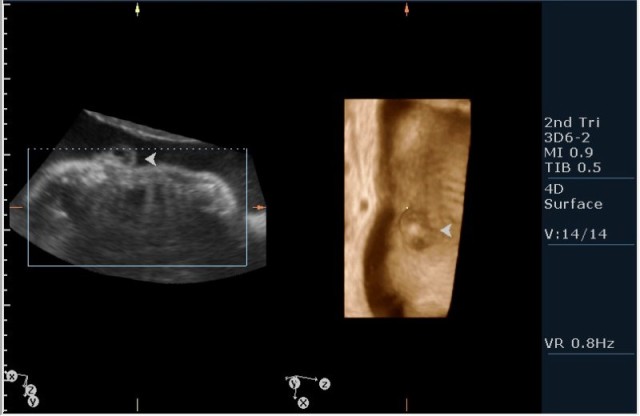

2.V-образное расщепление позвоночного столбы(рахисхизис)(на сонограмме №6 отчетливо виден дефект в поясничном отделе);

3.наличие дорсально расположенного содержимого спинномозгового канала(на сонограмме №7 видны мозговые оболочки).Это описывается как менингоцеле.

Ваш аппарат имеет режим объемной визуализации 3D/4D.Для постановки диагноза Вам в данном случае лучше было использовать не режим поверхностной реконструкции "Surface",а режим для визуализации скелета "Skeleton".В таком случае дефекты позвоночника будут видны отчетливее.

На сонограммах головы плода визуализаируется гифдроцефалия, патогенетически связанная со спинномозговой грыжей (менингомиелоцеле) представленная в 2D и 3D режимах. В режиме Skeleton не удалось получить "картинку презентационного качества", плод начал сильно вертется; но рекоммендация очень грамотная :idea: , спасибо за ваш пост!